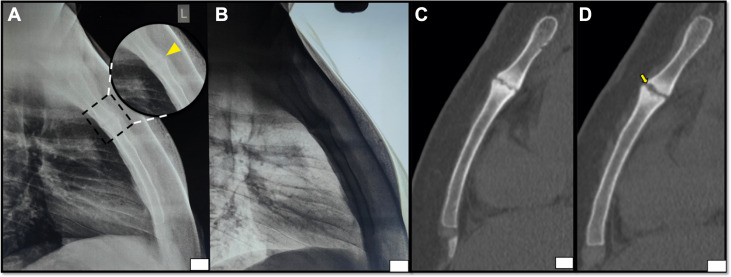

➤胸片(前后位+侧位):胸骨柄关节可见轻微侵蚀性改变及关节间隙狭窄(图1)。

➤胸部CT:确认胸骨柄关节存在关节旁侵蚀和硬化,双侧肺实质及纵隔无异常(图1)。

图1-胸片(A、B):标准模式(A)及灰度反转模式(B)胸部侧位片显示胸骨柄关节轻微侵蚀、关节面磨损(箭头)及骨质增生反应;非增强CT(C、D):骨窗矢状面多平面重建显示胸骨柄关节硬化、软骨下侵蚀(箭头)及关节间隙狭窄。